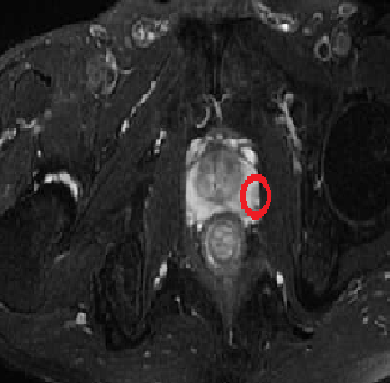

(李先生的磁共振影像)

然而,李先生还是不放心,先后杭州、上海跑了数家医院,最后决定做个穿刺。直到穿刺结果呈阴性,他悬着的心才落了地。后来,他在专科医生的指导下吃了些消炎药,再复查PSA,结果恢复了正常,证实了他的PSA升高确实与炎症有关。